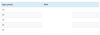

What are the categroies on the feverish illness guidelines

Colour

Activity

Respiratory

Circulation and hydration

Other

Mx of child at “green” on risk stratificiation for feverish illness?

Managed at home with appropriate care advice, including when to seek further help

Mx of child at “amber” on risk stratificiation for feverish illness?

Safety net or refer to paediatric specialist for further assessment

Safety net: verbal/written info about warning symptoms and how to access further care

Mx of child at “red” on risk stratificiation for feverish illness?

Admit to hospital

Key points for Mx of fever in child

Oral antibiotics should not be prescribed without identification of an apparent source of fever